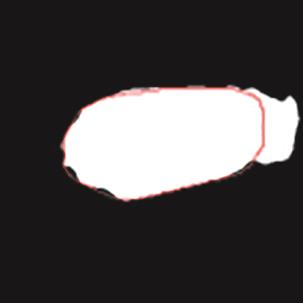

乳腺癌是全球女性最常见的恶性肿瘤之一,准确的病变分割对于乳腺癌的早期诊断与治疗具有重要意义。然而,由于病变形态的多样性以及超声成像机制的复杂性,现有基于深度学习的乳腺超声图像病变分割方法在分割准确性方面仍面临巨大挑战。为进一步提升乳腺超声图像中病变区域的分割精度,该文基于经典U-Net架构,提出了一种新型乳腺超声图像病变分割网络(CWSASKM-BBAM-Net)。首先,在网络中引入逐通道空间自适应选择核卷积模块(CWSASKM),根据不同通道的语义特征为每个空间位置自适应选择感受野大小,以增强多尺度信息的建模能力;然后,引入双向边界感知机制(BBAM),通过融合正向与反向注意力,对目标显著区域及其边界进行协同建模,同时逐步提升对非显著区域与病变区域的区分能力,以进一步强化边界信息的表达;最后,在3组公开乳腺超声图像数据集(BUSI、UDIAT和STU)上开展分割实验。结果表明:该方法在数据集BUSI上的杰卡德指数、精确率、召回率和Dice相似系数分别为71.97%、82.85%、81.40%和80.44%,较次优方法分别提升1.69、1.05、1.28和1.84个百分点;在数据集UDIAT上,这4项指标分别达到78.14%、88.31%、86.73%和86.10%,较次优方法分别提升了2.75、2.04、0.56和2.01个百分点;在外部数据集STU上,该方法也取得了优于其他方法的整体表现。实验结果表明,CWSASKM-BBAM-Net在乳腺超声图像分割任务中展现出更优的整体性能。